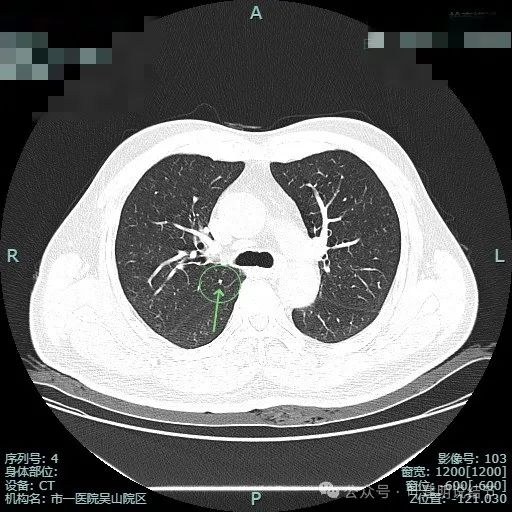

薄层影像:

病灶出现,瘤肺边界清,表面不平有分叶。

灶内密度不纯,整体轮廓清,瘤肺边界清楚。

明显分叶以及血管贴边并有异常增粗。

边缘毛刺,血管进入,灶边有细支气管扩张,整体轮廓与边界清。